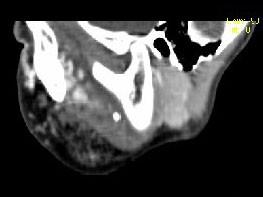

问题 男,12岁,左面颊肿大5年余,局部呈紫红色,CT如图所示,最可能诊断为 ( )

选项 A、慢性腮腺炎 B、下颌下腺慢性炎症 C、血管外皮瘤 D、动静脉畸形 E、蔓状血管瘤

答案 E